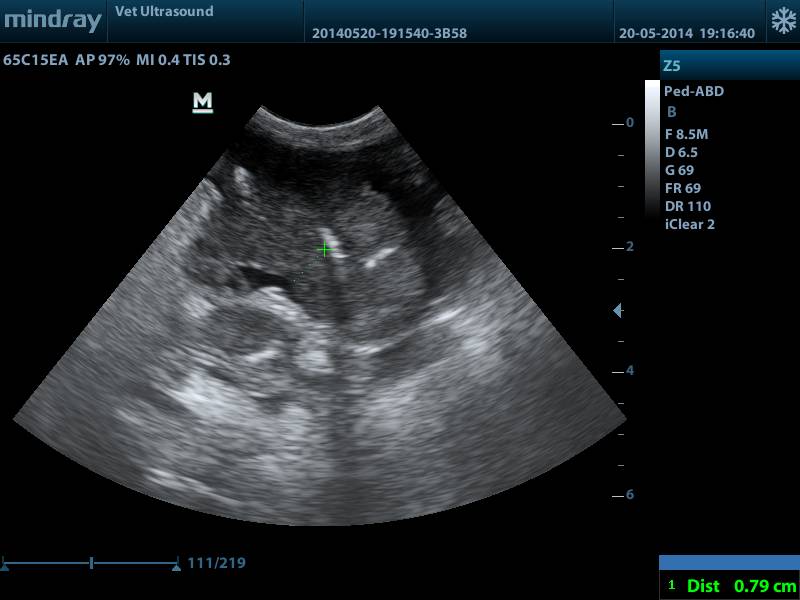

πάχος την μάζας 0.79 cm, φυσιολογικό πάχος λεπτού εντέρου 0.2 -0.3 cm

κόκκινο βέλος εντερικό περιεχόμενο, μπλέ βέλος μάζα με απώλεια της χαρακτηριστικής δομής του λεπτού εντέρου., πράσινα βέλη διογκωμένος μεσεντέριος λεμφαδένας.